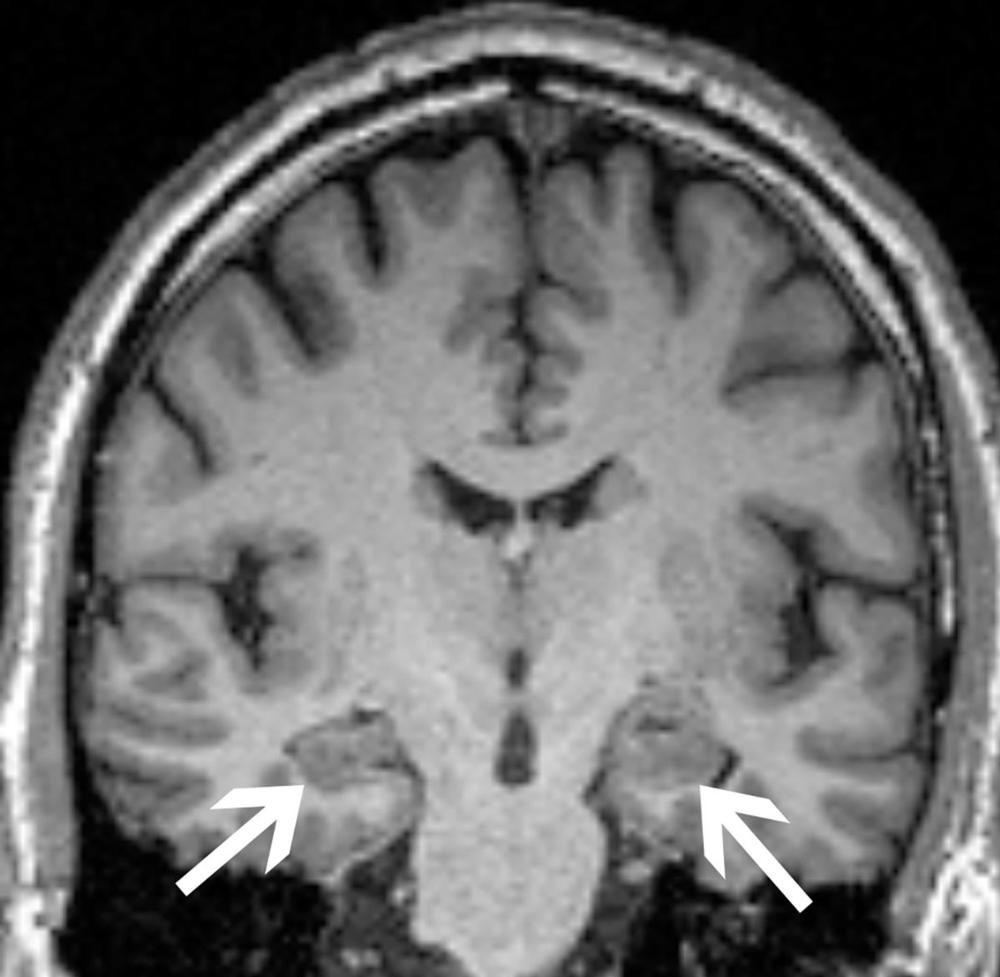

The researchers obtained brain MRIs to determine the baseline volumes of the hippocampus and the entorhinal cortex, two areas important to forming memories. They also tested for the presence of the ApoE4 allele, the most prevalent genetic risk factor for Alzheimer’s disease. Anxiety was measured with established clinical surveys.

As expected, patients who progressed to Alzheimer’s disease had significantly lower volumes in the hippocampus and the entorhinal cortex and greater frequency of the ApoE4 allele. Most notably though, the researchers found that anxiety was independently associated with cognitive decline.

Figure 2. Brain MRI of a 62-year-old man with mild cognitive impairment. His condition remained stable over the course of the study. His brain MRI demonstrates hippocampi of normal size (arrows). He was not a carrier of APOE4 and did not have an anxiety disorder.